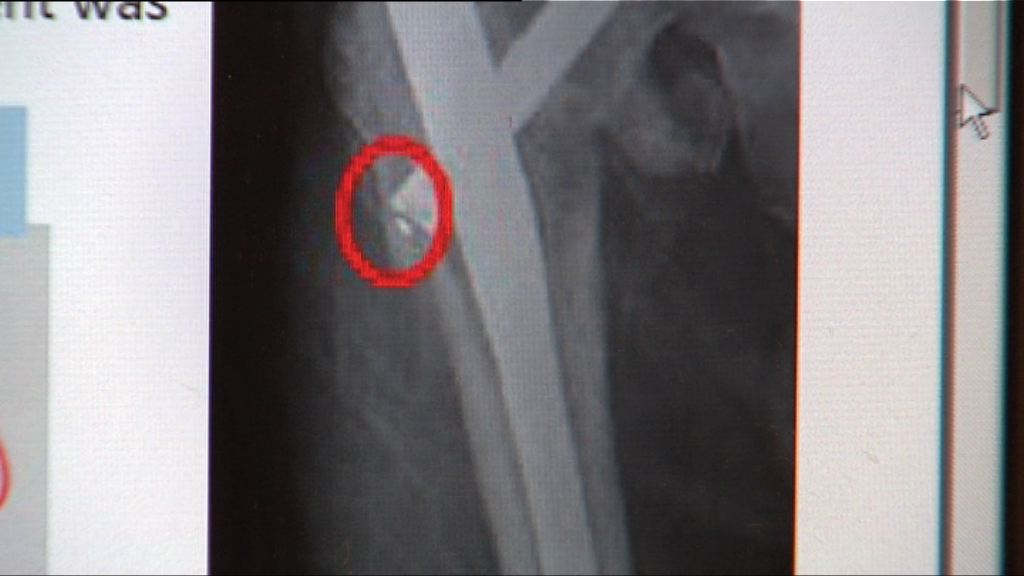

事件發生在七年前,73歲咽喉癌病人留院時,氣管造口被紗布封着後死亡。醫委會裁定主診醫生黃卓義專業失德成立,判詞指黃卓義未有留意護士多次出錯是不可原諒。